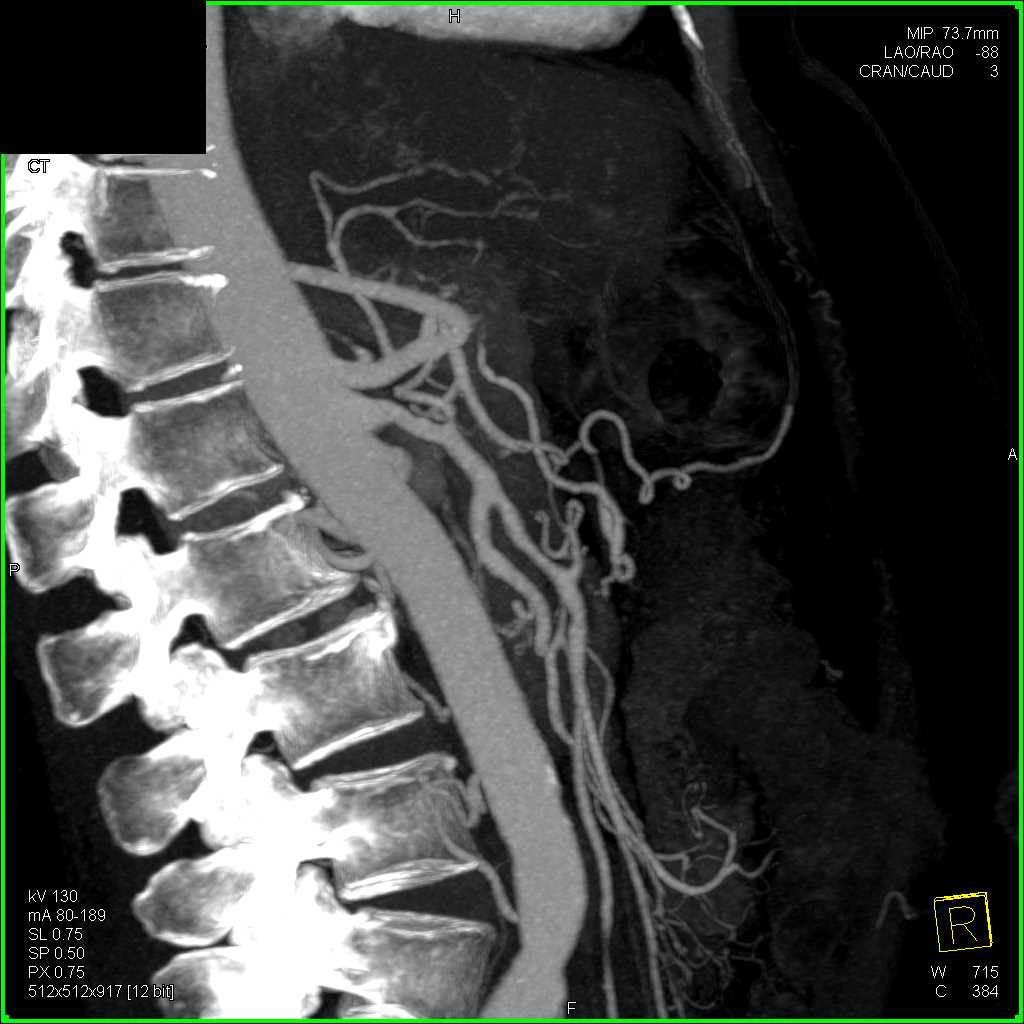

Neuroendocrine Tumor Body of Pancreas